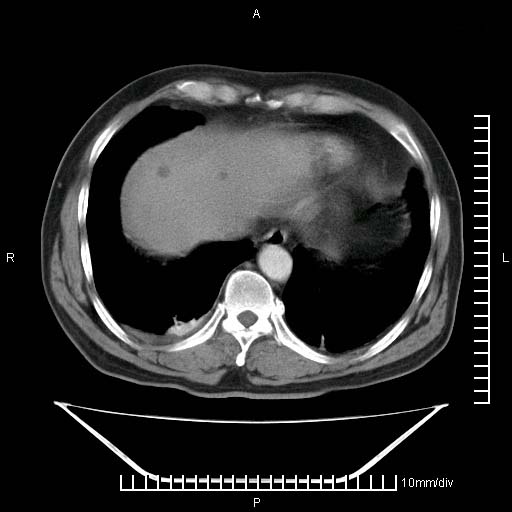

标题: CT25082:肝脏增强:男性,70岁 [打印本页]

标题: CT25082:肝脏增强:男性,70岁

患者以心脏疾病收住院,腹部无明显症状,b超查肝脏有占位。

考虑右肺下叶周围癌肝转移

肝内多发转移瘤,右下肺炎症并少量胸水。胃壁增厚建议胃镜,胰尾部“病变”为肠管。

1)肝脏多发性转移瘤(不排除胰尾癌转移所致可能)。2)腹水。3)右侧少量胸腔积液。

ct25082 结果:转移瘤

外院mr结果:胰尾恶性占位。